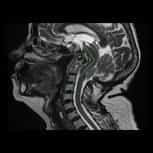

我們是一家位於西班牙巴塞隆納的國際專科醫療中心,不設分院,專注於精準且高品質的醫療照護。我們採用微創手術從病因治療Arnold-Chiari I型症候群、特發性脊髓空洞症與脊柱側彎等相關疾病,致力於為來自世界各地的患者帶來更安全、更有效的治療選擇。

你有Chiari畸形第一型、 脊髓空洞症或是脊柱側彎嗎?